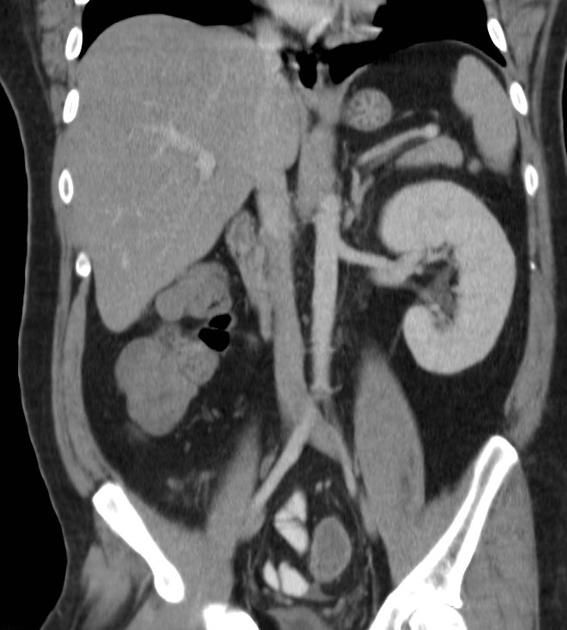

Renal agenesis is a rare condition in which there is absence of one or both kidneys. The exact aetiology behind this congenital condition is not known but different theories have been proposed including early vascular insult to the developing ureteric bud. In unilateral cases the person is usually asymptomatic and if not undergone antenatal screening this condition is usually picked up incidentally on abdominal imaging done for other reasons. If present bilaterally (traditionally known as the classic Potter syndrome) this condition is fatal in almost all the cases. Text Reference and Image Source: https://radiopaedia.org/articles/renal-agenesis